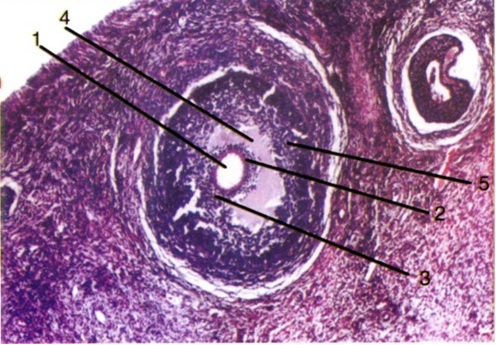

Сл. 4: Терциерен фоликул: 1 - ооцит од I ред;

2 - zona pellucida; 3 -cumulus oophorus; 4 - antrum folliculi;

5 - гранулозни клетки.